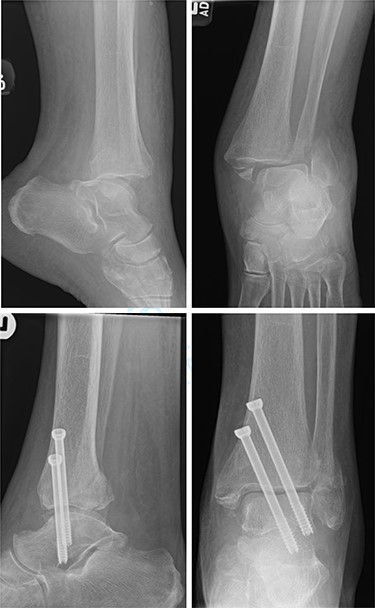

Overall, four out of six patients (66.7%) had satisfactory post-op radiographs with no evidence of talar shift, non/mal-union, widening of the syndesmosis or screw loosening (Figs 1 and 2).

Top—Fracture dislocated bimalleolar ankle fracture. Bottom—6 weeks post-operatively showing maintained tibiotalar alignment.